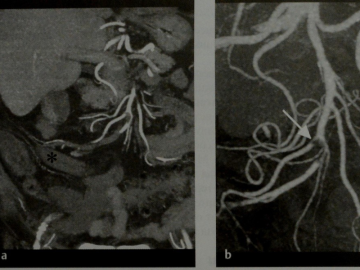

Наиболее точный метод диагностики инфаркта кишечника — это ангиография. В сосуды брюшной полости через катетер вводят рентгеноконтрастное вещество и изучают его распределение. Таким образом можно увидеть участки кишечника, оставшиеся без кровоснабжения.

Другой современный метод диагностики — компьютерная томографическая ангиография. Изображение сосудов выстраивает компьютер на основании полученных томографом срезов.